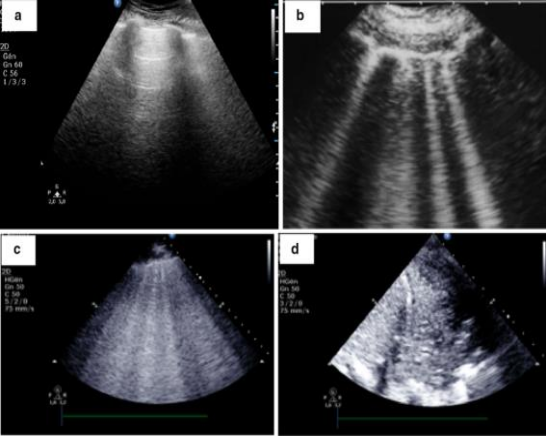

(2)肺部超声:根据肺内含气和含水的情况来判断,如下图所示,黑色部分是肺通气良好区域,如果有间质轻度水肿,可以出现黑色和白色相间;白色部分是严重间质水肿/肺泡水肿,灰色部分为实变区域。

图片

还可以通过超声对肺组织的通气程度进行评估。a:出现与胸膜相平行的A线或2条以内的B线通常显示肺组织通气良好;b:出现多条垂直于胸膜有明确间距的B线(B1线)则提示肺组织通气减少;c:出现多条合并的B线(B2线),并且其间距<3 mm则提示肺组织通气严重不足;d:出现动态支气管空气征则提示肺实变。

根据肺部超声可以实现肺可复张性的半定量评估,但其也具有一定的局限性,可能低估肺复张情况。由于需要在肺内12个区域进行评估,所以操作和评分比较复杂,应用受到一定的限制;而且受操作者的经验影响较大,患者因素(胸壁皮下脂肪厚度、胸壁皮下气肿等)也影响准确性,且不能区分正常通气或过度通气,不能作为肺复张评价的唯一指标。